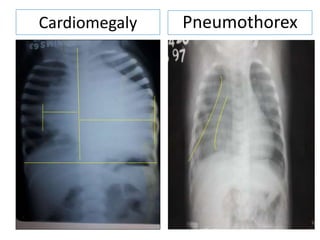

Cardiothoracic ratio Cardiomegaly Causes

Cardiomegaly = CT ratio>50%

Cardiomegaly Pneumothorex

Cardiothoracic ratio CardiomegalyCauses •Heart Valve Disease •Cardiomyopathy (disease of the heart muscle) •Pulmonary Hypertension •Pericardial Effusion (fluid around the heart) •Thyroid Disorders •Hemochromatosis (excessive iron in the blood) •Other rare diseases like Amyloidosis •Viral infection of the heart •Kidney disease requiring dialysis •HIV infection •Diabetes •Alcohol or cocaine abuse Cardiomegaly = CT ratio>50%